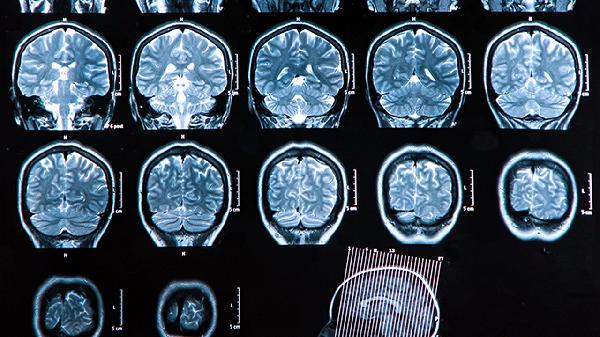

脑溢血术后康复期间应保持均衡饮食,适当增加优质蛋白和维生素摄入。保证充足睡眠,避免过度劳累。定期复查头颅CT或MRI,监测脑部恢复情况。严格遵医嘱进行康复训练,不可操之过急。如出现肢体麻木加重、意识改变等情况需立即就医。康复过程需要耐心,多数患者经过系统治疗可逐步恢复部分神经功能。